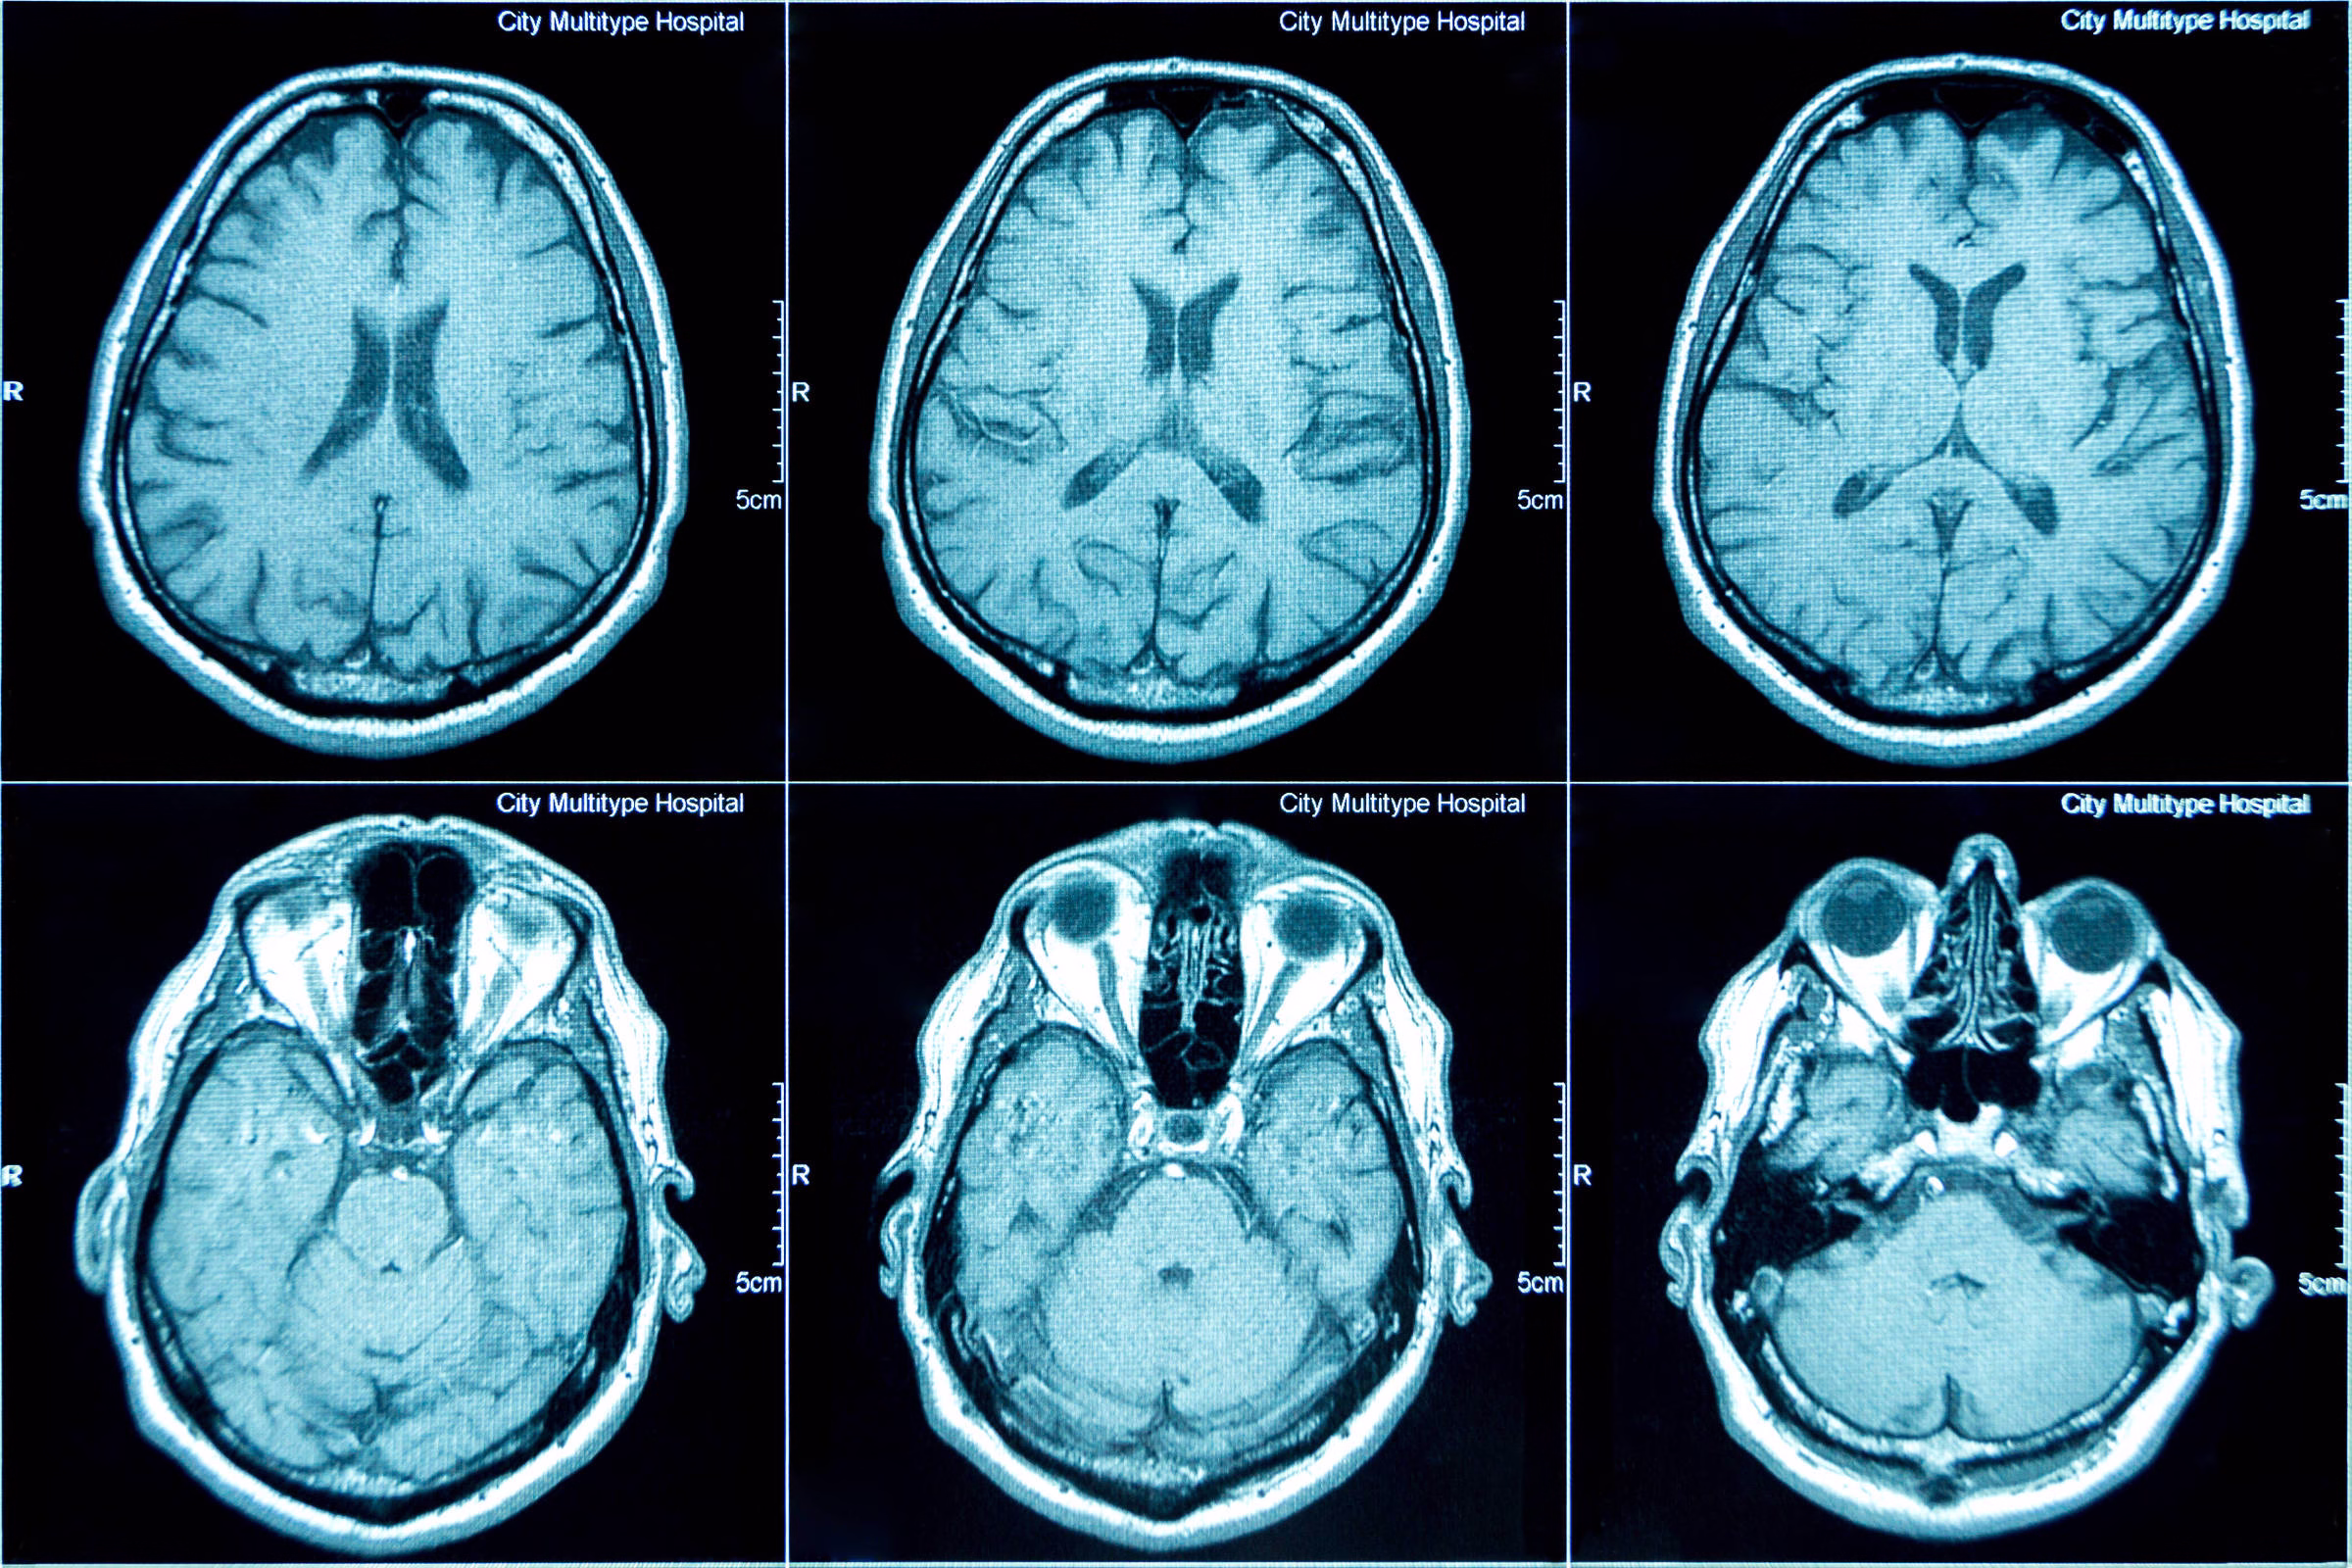

A droga atua se ligando aos amiloides, reduzindo a formação de placas da proteína anormal no cérebro de pacientes –mas sem curar ou reverter danos causados pela doença.

Pessoas com Alzheimer têm um acúmulo de proteínas anormais no cérebro – conhecidas como amiloide e tau. Mas até recentemente não se sabia qual era a relação direta entre essas proteínas.

Segundo o estudo, pacientes com Alzheimer têm células cerebrais inflamadas por causa do acúmulo de amiloides anormais entre os neurônios, que alteram sua química interna.

Esses amiloides formam “placas”, enquanto a proteína tau se acumula em feixes fibrosos, ou “emaranhados”. Isso leva as células cerebrais a produzir uma molécula chamada MEG3 –que, ao ser bloqueada pelos pesquisadores, salvou os neurônios da morte.